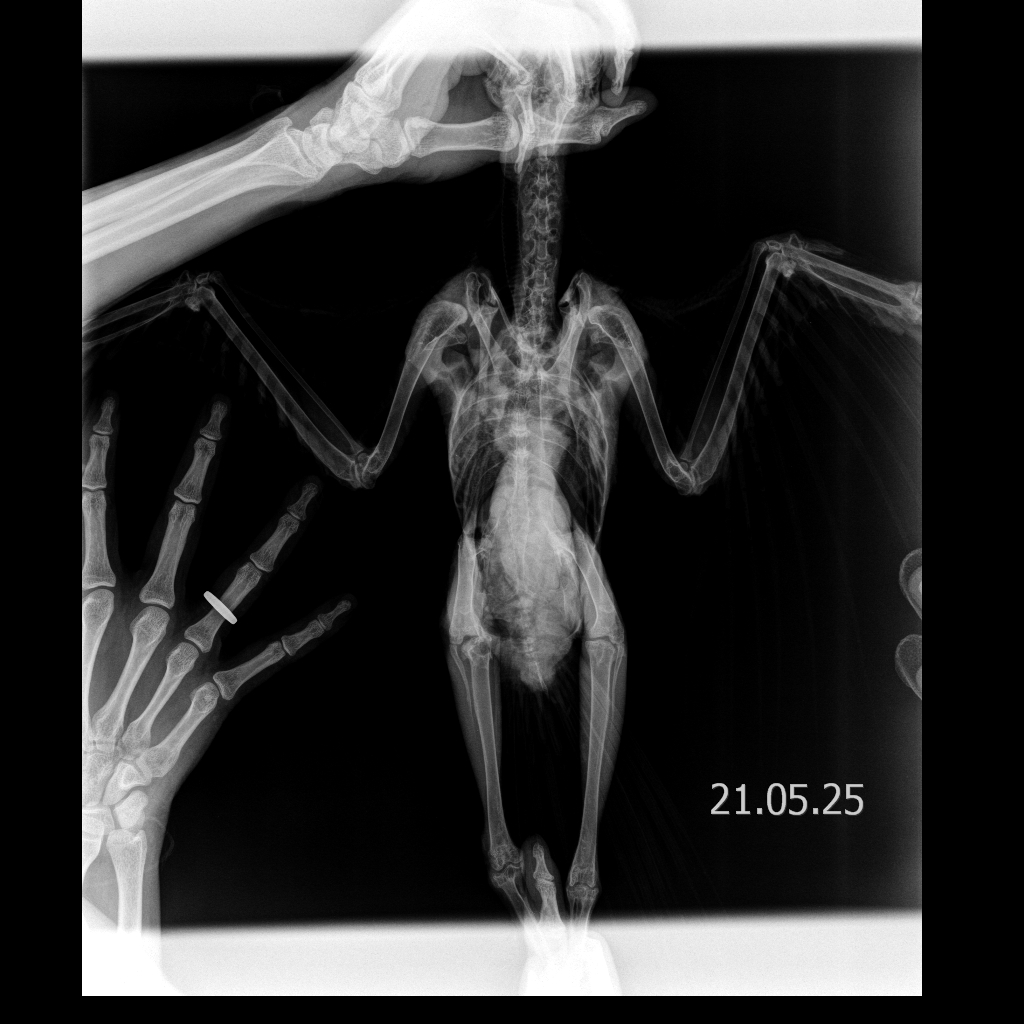

Рентгеновский снимок Фени. Фото предоставлено Сергеем Быковым

Выяснилось, что у Фени четыре перелома позвоночника в трех отделах и раздроблена спина  — врачи сказали, что его нужно однозначно усыплять, потому что птица не выживет и будет мучиться. Обычно при таких травмах животные погибают. Но я отказался усыплять Феню.

Пока конструкция подгонялась и обустраивалась под него, Феня так рассек себе суставы, что прямо из суставных сумок торчали косточки. Помимо этого, спустя три месяца у него начались ужасные воспаления в костях. Изначальные проблемы с позвоночником уже, казалось, были решены, и вот его начала убивать новая беда.  Я искал специалистов, но не нашелся никто, кто мог бы помочь.

Я решил зашить их сам: заказал хирургический набор с иглами и нитями, проанестезировал Феню. Мне на ум пришла собственная методика, чтобы Феня больше не ковырял, и я сделал так, чтобы нитки торчали не сверху, а были внутри сустава. У Фени действительно все зажило. Правда, у него периодически все еще болит спина так, что он сдирает перья на спине. Суставы у него все равно открыты, но уже не воспалены — теперь там даже растут перышки, хотя раньше было просто мясо.